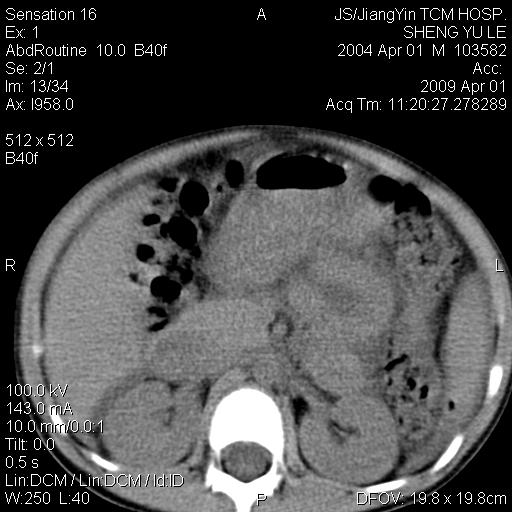

m,5岁。尿痛尿频数天。既往无病史。ct平扫腹盆腔积液。膀胱壁明显增厚。另可见心包增厚。wbc5万,骨髓穿等结果。请指教。

膀胱影像表现结合临床应该是急性膀胱炎症,但为什么有腹水呢?双肾输尿管无扩张,泌尿系压力应该不大不至于引起尿外渗,应该是腹膜感染引起的,但楼主没有提及相关症状,腹膜及膀胱结核?患者白细胞5万(结核不至于这么高啊),脾脏增大,是不是有白血病?进一步检查。。

腹水,膀胱壁增厚,wbc5万,结合临床,支持感染性疾病---感染性腹膜炎、腹水,急性膀胱炎,败血症。期待结果。